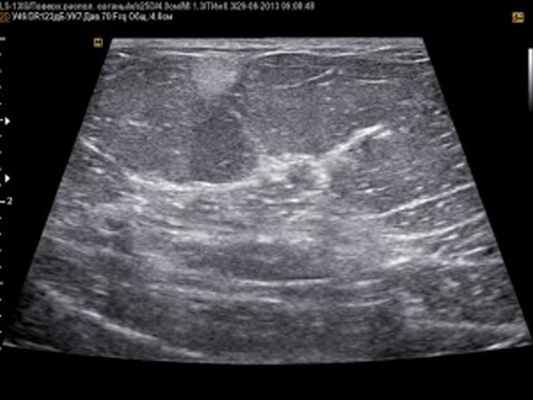

- Ультразвуковое исследование для оценки внутреннего строения поверхностных жировых опухолей.